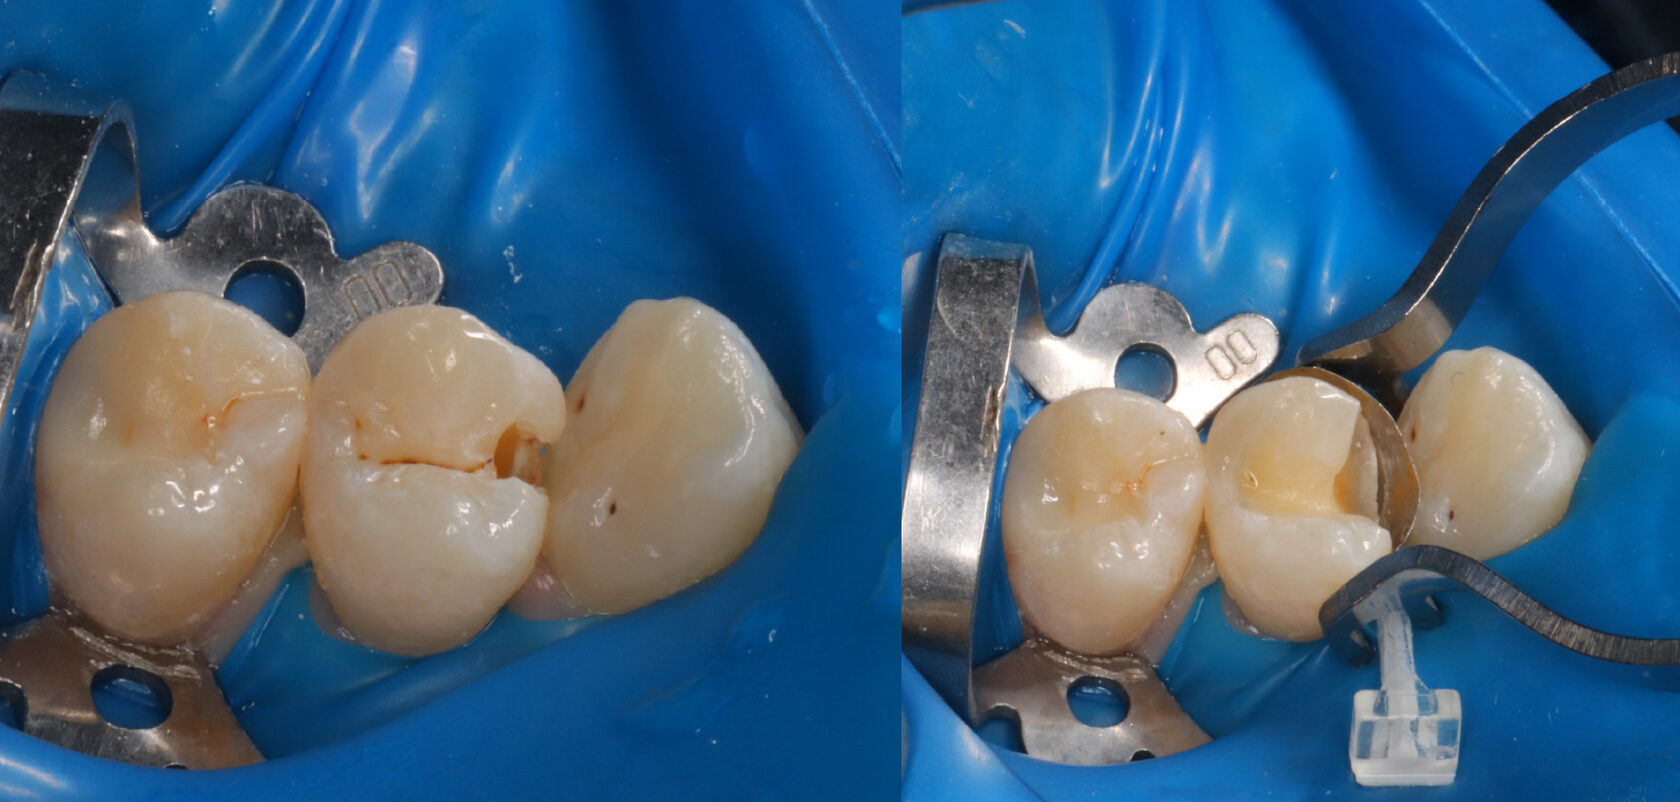

Случай достаточно классический, но осложнен расположением соседнего зуба, клыка. он развернулся на 45 градусов, поэтому мешает и пациенту, качественно прочистить зуб, и врачу в лечении.

Лечение кариеса - это грамотно обезболить, изолировать зуб, аккуратно убрать кариес, не задев соседний зуб, далее поставить специальные матрицы, для того, чтобы воссоздать контактный пункт и потом также бережно заполировать эту стенку.